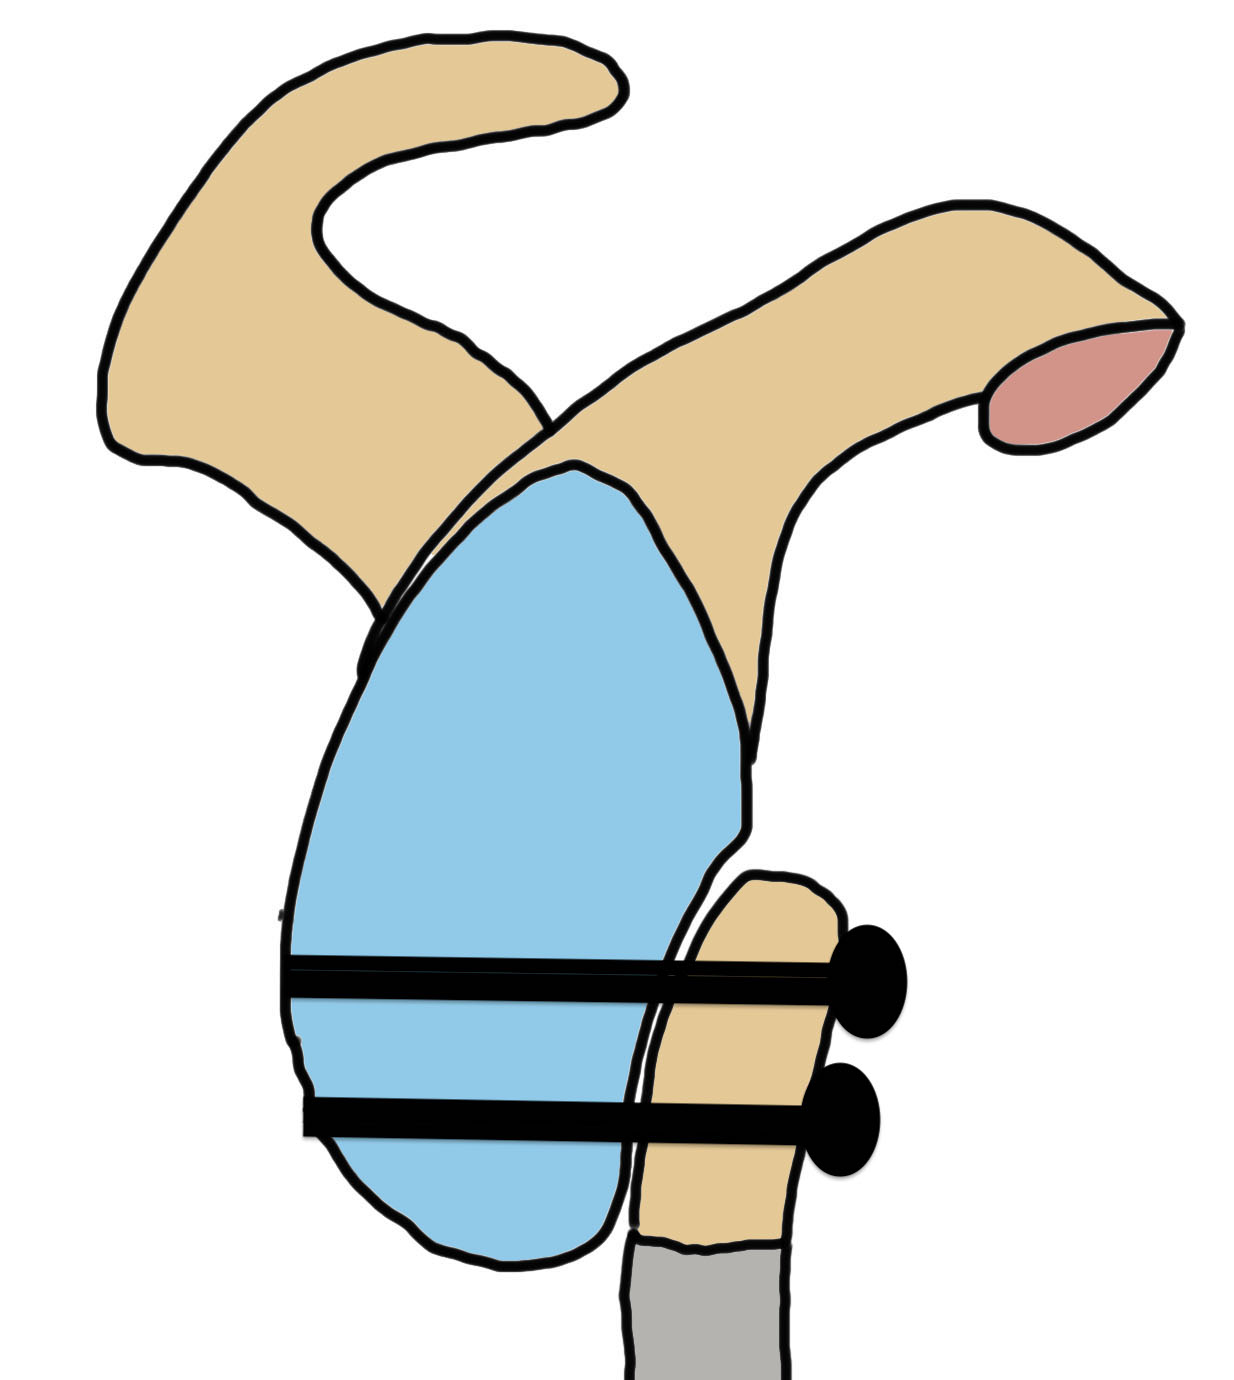

Bone block positioning

Concepts

- coracoid must not overhang medial to avoid osteoarthritis

- coracoid < 5 mm medial to glenoid rim

- coracoid lower half of glenoid 2 - 5 o'clock

- fixation screws purchases posterior glenoid cortex

- screws do not penetrate articular surface

Traditional Latarjet v Congruent arc

- align concave inferior surface coracoid with medial concave glenoid

- graft is thinner in this position, making screw fixation more difficult